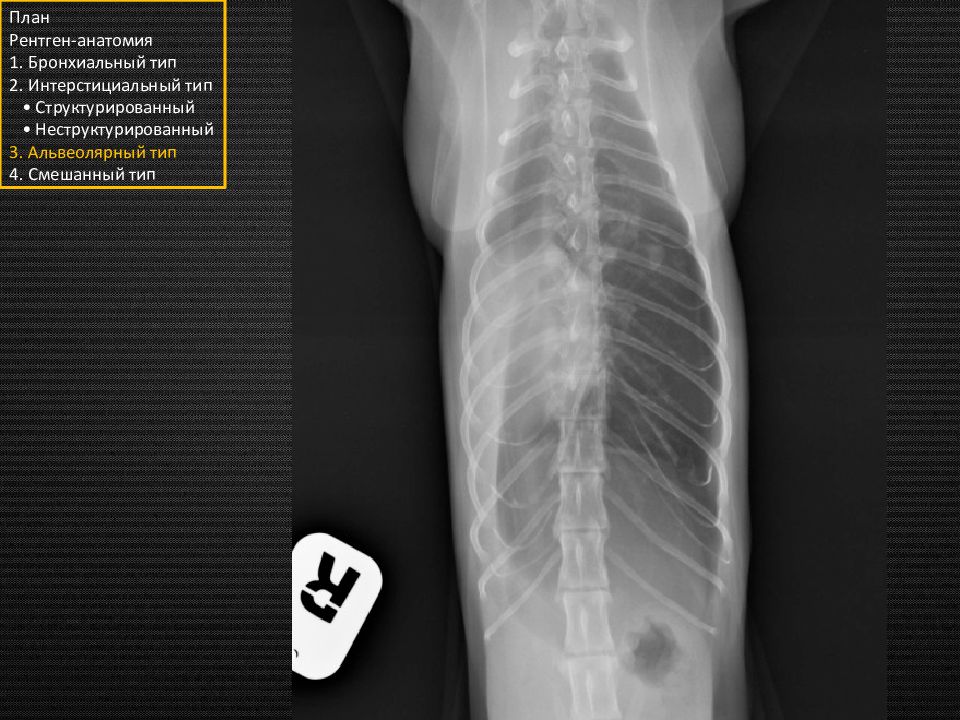

Слайд 5

Собака. Грудная клетка нормальной формы План Рентген-анатомия 1. Бронхиальный тип 2. Интерстициальный тип • Структурированный • Неструктурированный 3. Альвеолярный тип 4. Смешанный тип